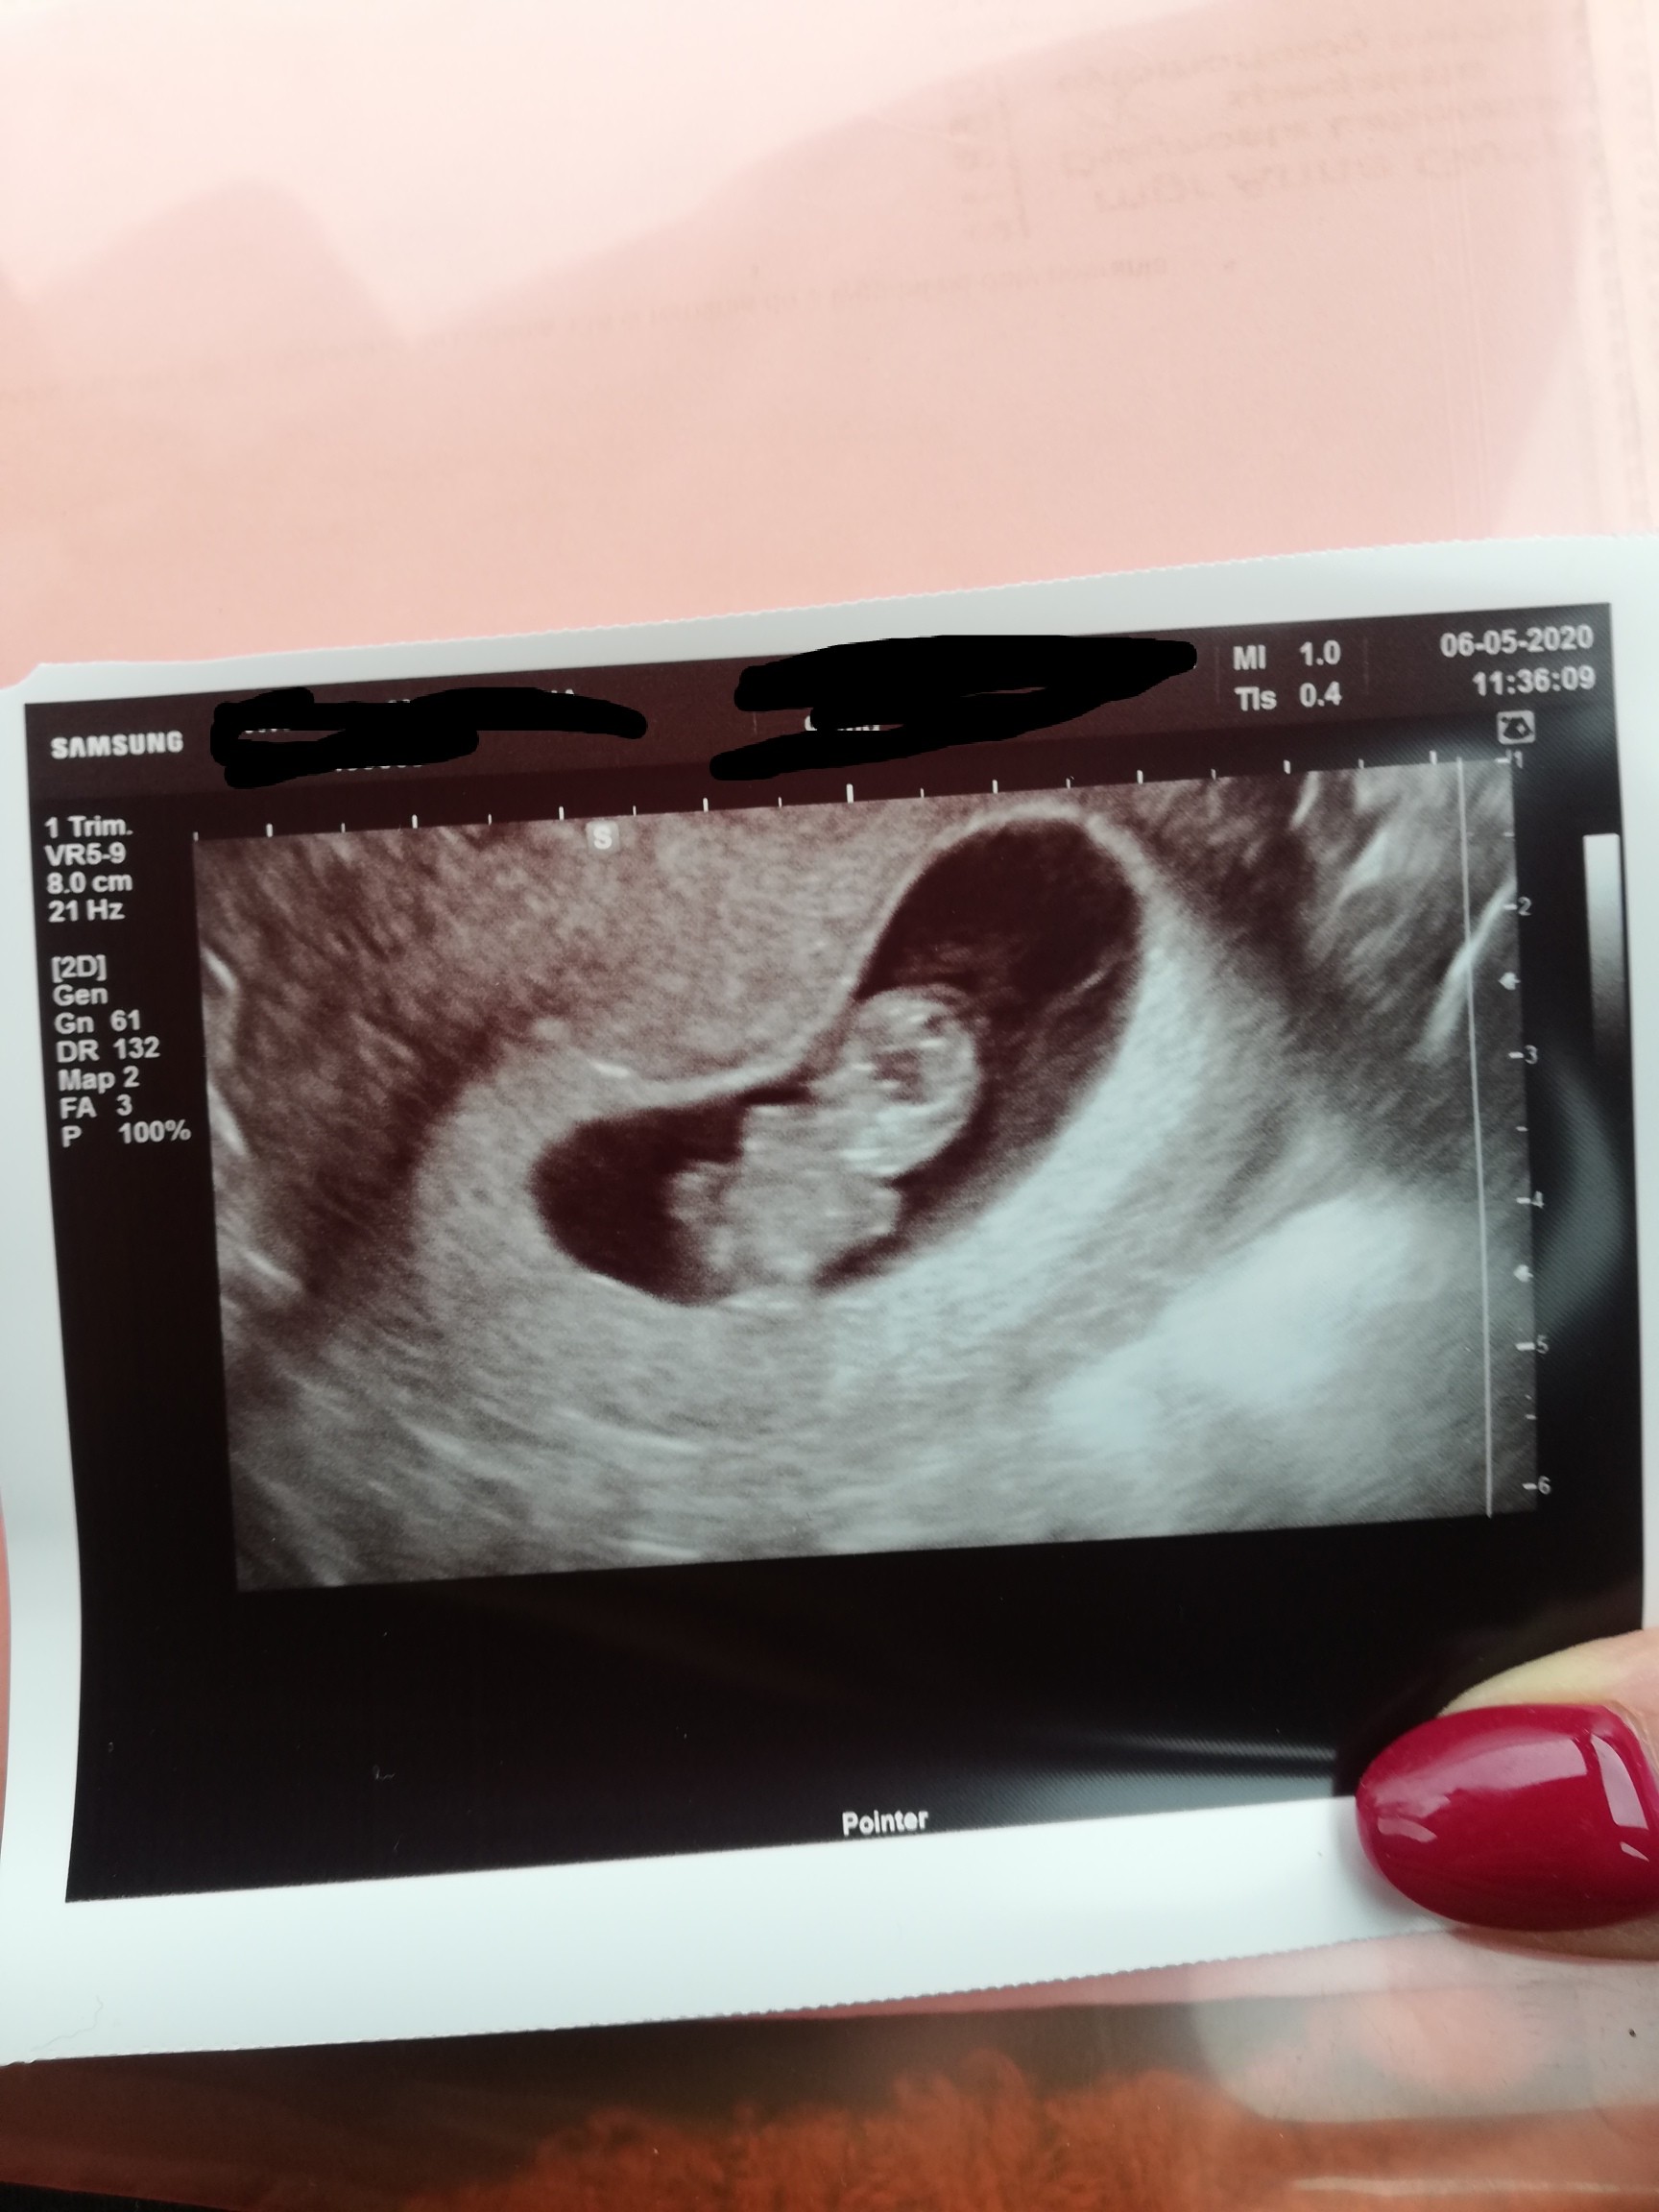

Ja po wizycie! ❤ Serduszko bije. Tętno 160 🤭 ponoc idealne. Maluszek ruchliwy. Widzialam jak rusza rączkami i nóżkami ❤❤❤ wiercił się tak strasznie, ze pani się smiala ze go nie zmierzy bokiem.. Próbowała z 2 minuty, ale nie dało sie bokiem 😂 ma 2.5cm. Mocno kosmówka siedzi. Nic sie nie powinno dziać. Mowi, ze jak mdłości przeszly to juz nie powinny wracać i tylko teraz zachcianki i rosnący brzuch ❤ ogólnie mega jestem zadowolona ❤

Wedlug usg 9+1 dzisiaj :)